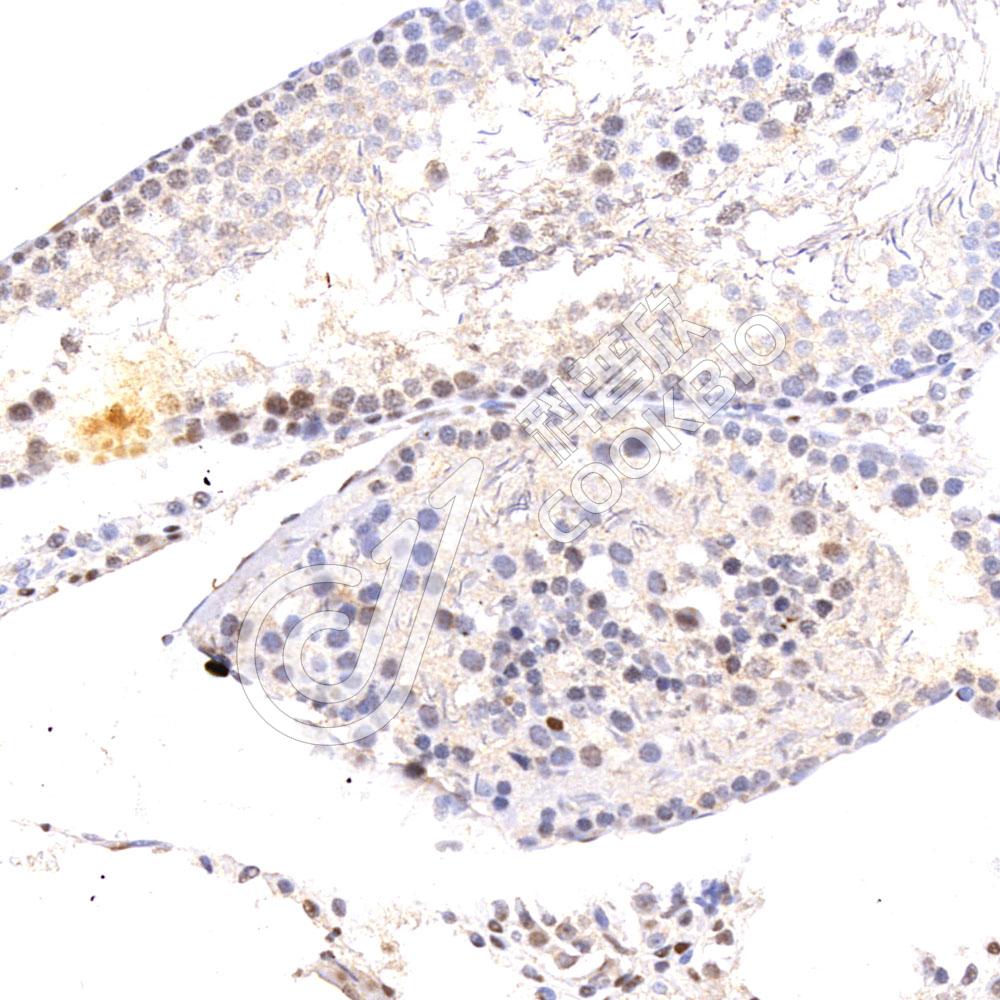

IHC检测p21蛋白(货号 K545459).

样品: 小鼠睾丸, 4%多聚甲醛 (货号KSG1101) 固定12-24小时.

抗原修复: 柠檬酸抗原修复液(干粉, pH 6.0) (KSG1201), 高压锅均匀喷气计时2分钟.

—抗: 1: 800稀释, 4℃ 孵育过夜.

二抗: S-vision免疫组化多聚二抗(山羊抗小鼠), 即用型(货号KB3903), 室温孵育20分钟.